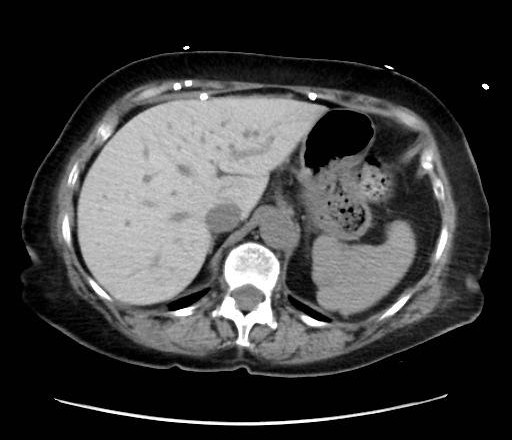

- Non-contrast axial CT through the upper abdomen.

- The liver (image-left, patient-right) demonstrates diffusely increased parenchymal attenuation relative to spleen (image-right, patient-left).

- Liver contour appears smooth, no focal mass identified at this level.

- Spleen (image-right, patient-left) of normal size and attenuation.

- Stomach fundus (image-right, patient-left) partially distended with air-fluid level.

- No ascites visible.

- No intrahepatic or extrahepatic biliary ductal dilatation.

- Osseous structures and visualized lung bases appear unremarkable at this slice.

Diffuse hepatic parenchymal hyperattenuation due to amiodarone deposition (amiodarone liver). The liver is abnormally hyperdense on a non-contrast CT compared to the spleen, which is a classic imaging feature of amiodarone-induced hepatic iodine deposition. The attenuation difference eliminates common diffuse hypodensity causes such as steatosis, iron overload, or Wilson’s disease. Context consistency: Consistent. The uploader’s diagnosis of "Amiodarone Liver" directly matches the imaging appearance. Confidence: 90%.